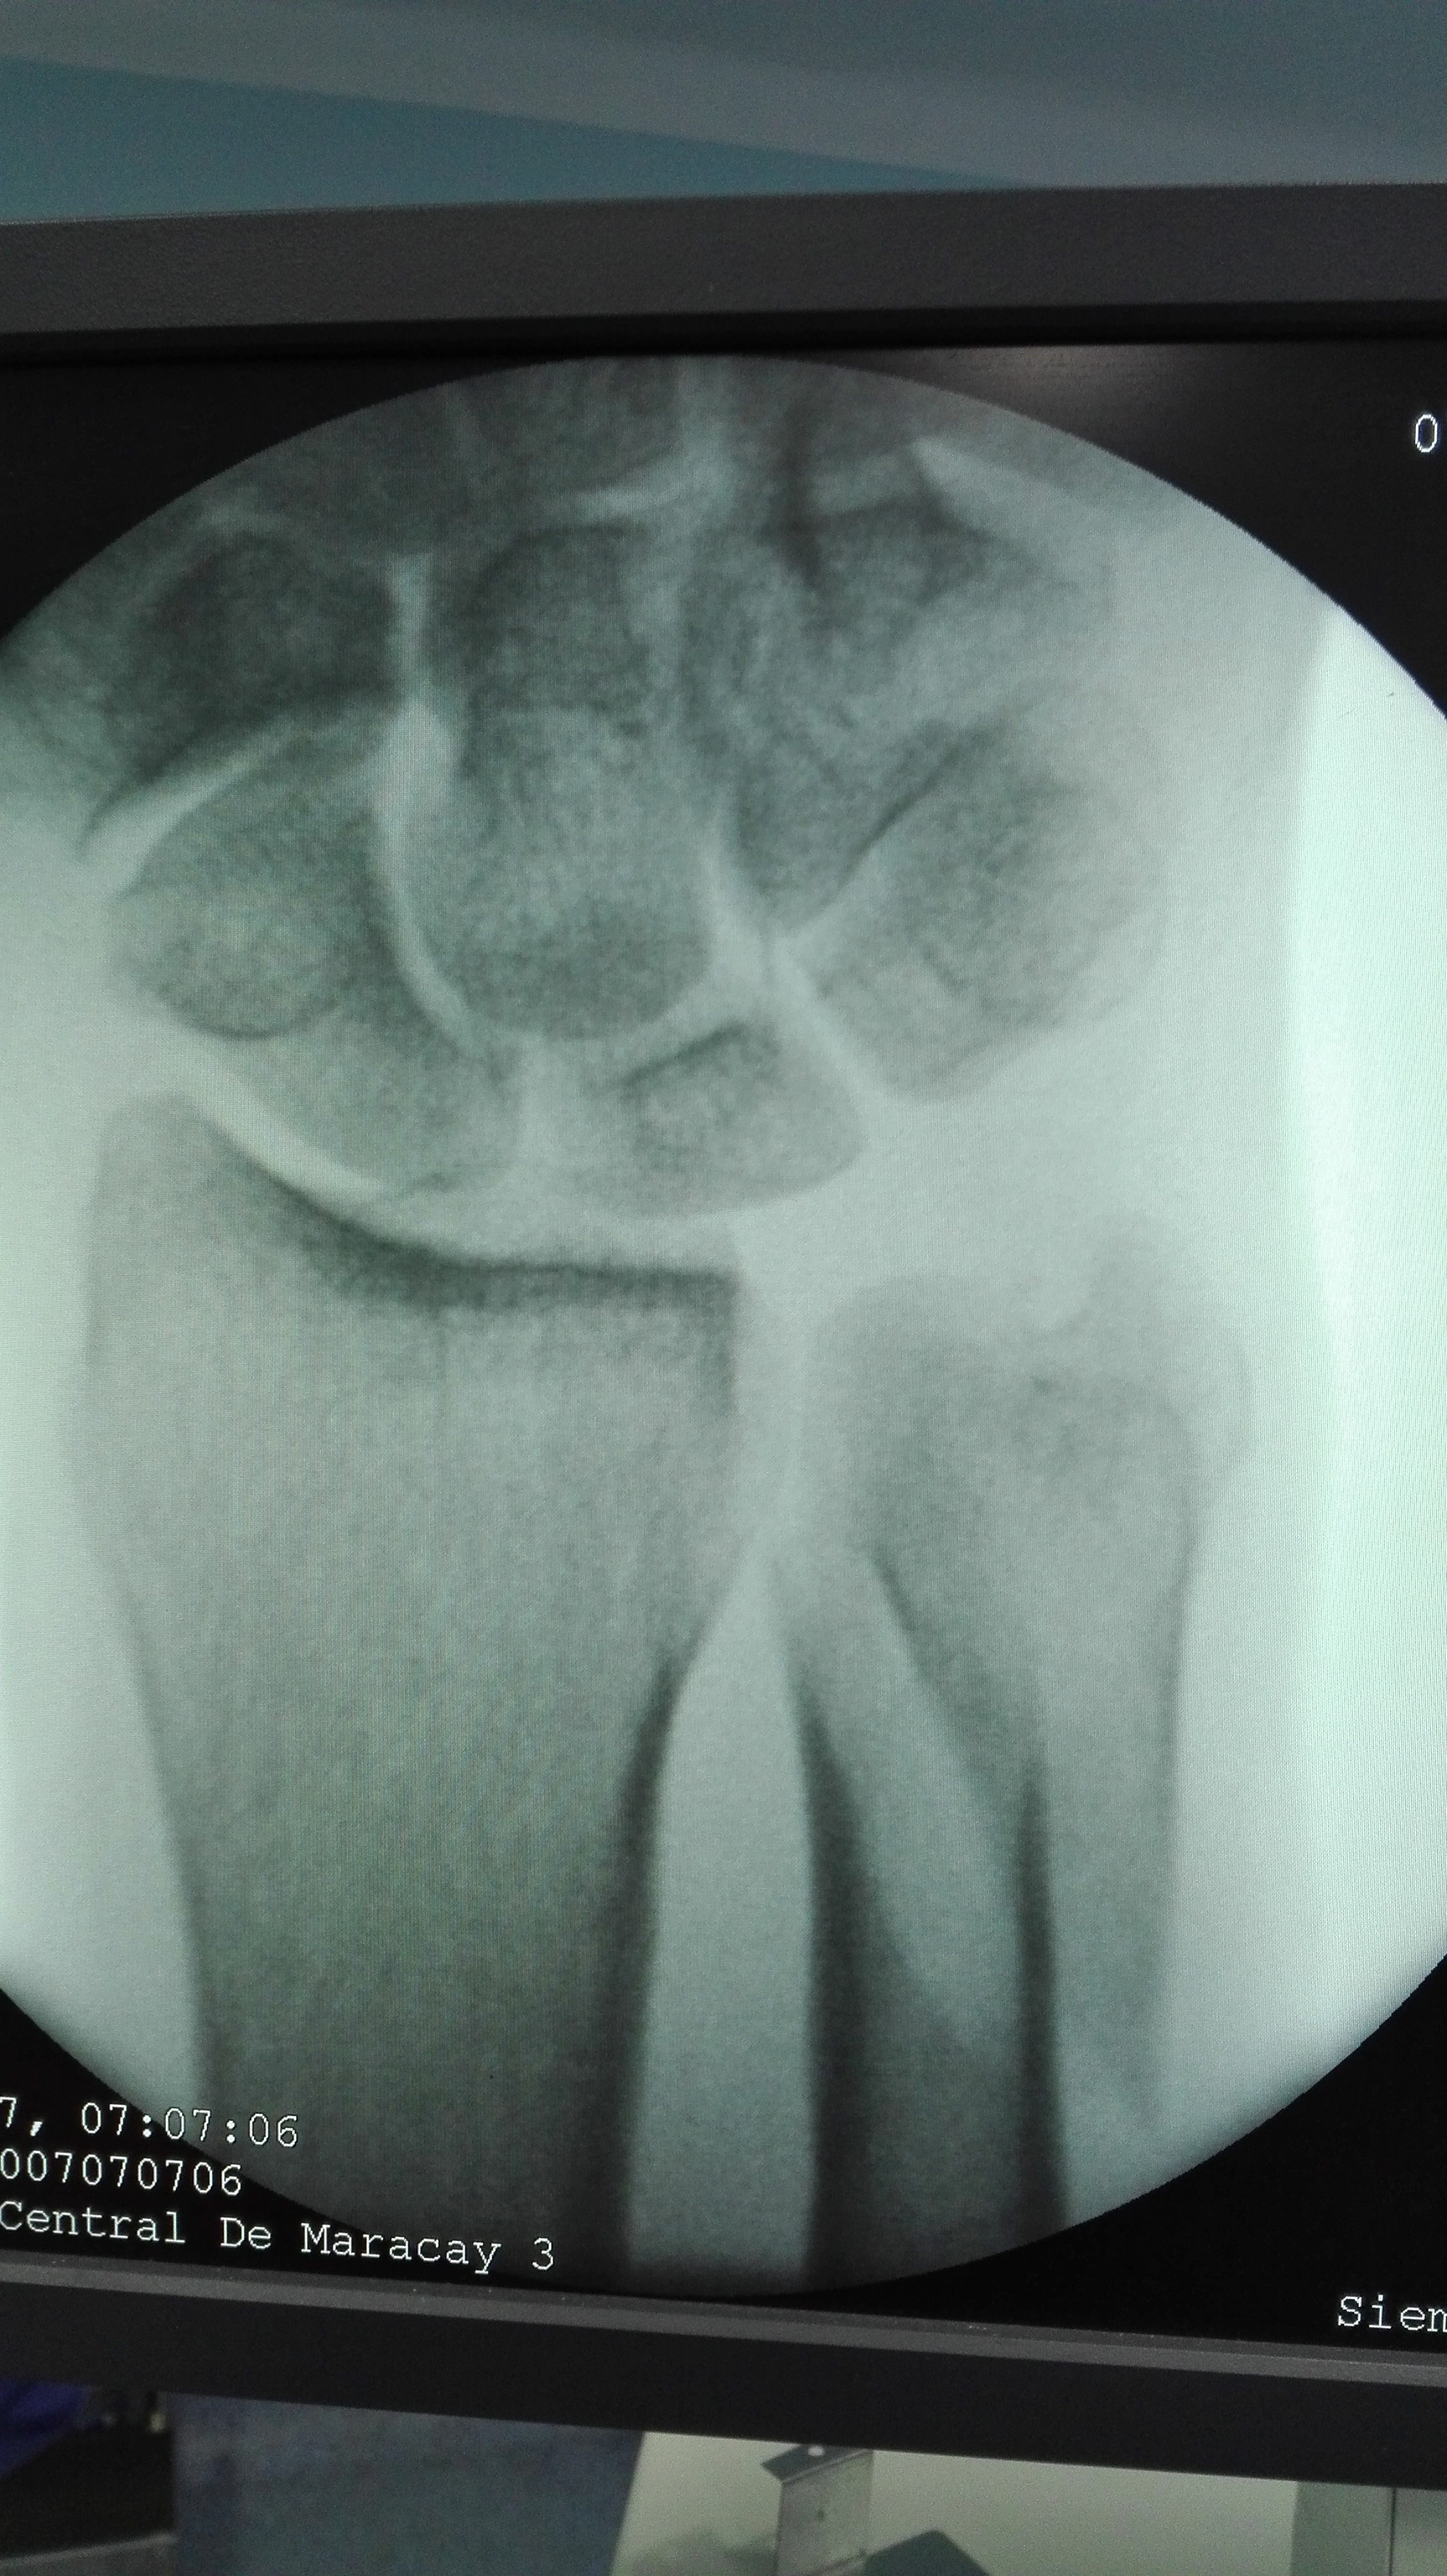

Recently we had the opportunity to have surgery for a fracture of the ulna, they are not very frequent in isolation as most of the time they present together with fractures of the radius. The osteosynthesis of these fractures may seem easy but any error can make it difficult for patients to perform their manual tasks in the same way as before. Today we will talk about: The Cubitus.

The most common ulna lesions occur in the area near the wrist. If a person falls and puts his hands to avoid hitting his head, the ulna will receive the stress of the impact and may fracture if the force exceeds its elastic resistance. This injury can occur in conjunction with others, such as a radius fracture, dislocation of the wrist, dislocation or distortion of the elbow and the so-called Colles fracture, among others affecting the bones of the forearm, wrist or hand.

Although ulna fracture is very common in older people, age is not an exclusive condition for this type of injury. There are several factors that can affect the characteristics of a fracture of the ulna, since two apparently equal accidents differ in the force of the impact, the angle of the blow, the age of the subjects, and so on. With respect to the type of fracture, it is possible to differentiate between coronoid process, stress, avlusion, displaced, comminuted, incomplete and olecranon.